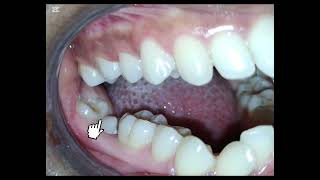

Clinical Tip 2: Bite Ramps, Coil Spring, E Chains, working together. Squirrel Teeth Cross Bite Crowd